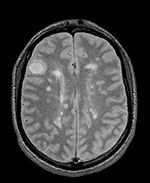

Slicer Registration Library Case 04: Intra-subject Brain MR of Multiple Sclerosis: Multi-contrast series for lesion change assessment

This scenario occurs in many forms whenever we wish to assess change in a series of multi-contrast MRI. The follow-up scan(s) are to be aligned with the baseline, but also the different series within each exam need to be co-registered, since the subject may have moved between acquisitions. Hence we have a set of nested registrations. This particular exam features a dual echo scan (PD/T2), where the two structural scans are aligned by default. The post-contrast T1-GdDTPA scan however is not necessarily aligned with the dual echo. Also the post-contrast scan is taken with a clipped field of view (FOV) and a lower axial resolution, with 4mm slices and a 1mm gap (which we treat here as a de facto 5mm slice).

Unregistered baseline data: PD vs. T1Gd Unregistered followup data: PD exam 2 vs. exam 1

Registered baseline data Registered followup data